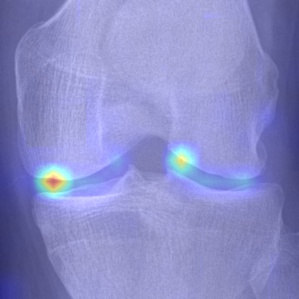

Refer to caption

(a) DenseNet-201

(b) ResNet-18

(c) VGG-11

(d) Tiuplin et al. [12]

(e) Wang et al. [16]

(f) Our model

Figure 8: Comparison of attention maps obtained from the last layer using different learning models.

To visualise the regions that contributed to the decision of each model, the Grad-Cam technique [36] was used. The attention maps obtained are presented in Fig. 8. As can be noticed, all evaluated models show a certain sensitivity to regions that involve early KOA (KL-2) characteristics (osteophytes and JSN). However, DenseNet, ResNet, and VGG models also exhibit a reaction to background noise, which may negatively impact the classification performance. To a lesser extent, the Siamese-based models [12] and [16] exhibit more reaction to areas affected by OA. Conversely, our proposed approach focuses more on regions affected by OA, which demonstrates that with a well-designed position embedding layer, it is possible to make the model concentrate on specific areas concerned by OA. It is noteworthy that during the data preprocessing of Siamese-based networks ([12] and [16]), it is often necessary to crop key patches as an input pair to the network. While this significantly reduces the parameter size of the model, it results in a loss of information from the input image. Especially for medical images, the integrity of global image information is vital and can enhance the model’s decision confidence in clinical applications. In comparison to those methods, our approach simply encourages the model to pay more attention to the key patches, but it also considers the texture information of other patches to some extent. Additionally, thanks to the ordered position embedding of key patches, our model handles their sequential information better. As can be seen in Fig. 8(d) and Fig. 8(e), compared to [12] and [16], our model is able to draw attention to locations of possible osteophytes in the joint space, which is more consistent with medical opinion.